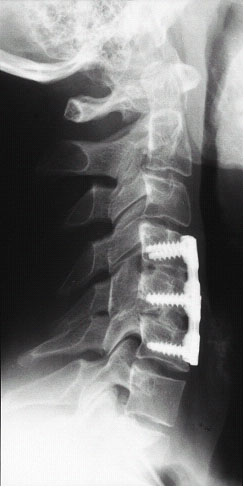

Abb. 3+4 von links

Zustand nach operativer Versorgung des Bruches mittels Titanplatte, welche mit 6 Schrauben in den 4.,5.und 6.Halswirbelkörper verankert sind. Die beiden Bandscheiben ober und unterhalb des gebrochenen Wirbelkörpers wurden entfernt und durch Eigenknochen aus dem Beckenkamm des Patienten ersetzt. (linkes Bild) Rechts das Röntgenbild nach ca. 8 Monaten, eine knöcherne Verrbindung zwischen den verschraubten Wirbelkörpern ist entstanden.